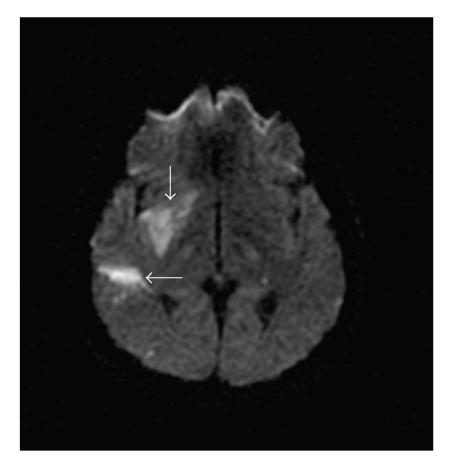

Background. Although thrombolytic therapy has been shown to be beneficial to stroke patients, the effectiveness of intravenous thrombolysis in ischemic stroke patients with ventricle myxoma is unknown. Case Description. A 22-year-old woman with left hemiplegia was sent to the emergency department at a teaching hospital. The magnetic resonance angiography showed occlusion of the right middle cerebral artery, and the echocardiography showed a mass in the left ventricle. Intravenous recombined tissue plasminogen activator (rt-PA) was administrated, and the postthrombolysis transcranial Doppler exam showed that her right middle cerebral artery was circulative. The patient's condition improved gradually, and no complication was observed up to 16 months of follow-up. Conclusion. Intravenous rt-PA is a reasonable treatment for stroke patients with ventricle myxoma.

背景。尽管溶栓治疗已被证明对中风患者有益,但静脉溶栓治疗在患有心室黏液瘤的缺血性中风患者中的有效性尚不清楚。病例描述。一名22岁左侧偏瘫女性被送往一家教学医院的急诊科。磁共振血管造影显示右大脑中动脉闭塞,超声心动图显示左心室有肿物。给予静脉注射重组组织型纤溶酶原激活剂(rt-PA),溶栓后经颅多普勒检查显示其右大脑中动脉有血流。患者病情逐渐改善,随访16个月未观察到并发症。结论。静脉注射rt-PA是患有心室黏液瘤的中风患者的合理治疗方法。